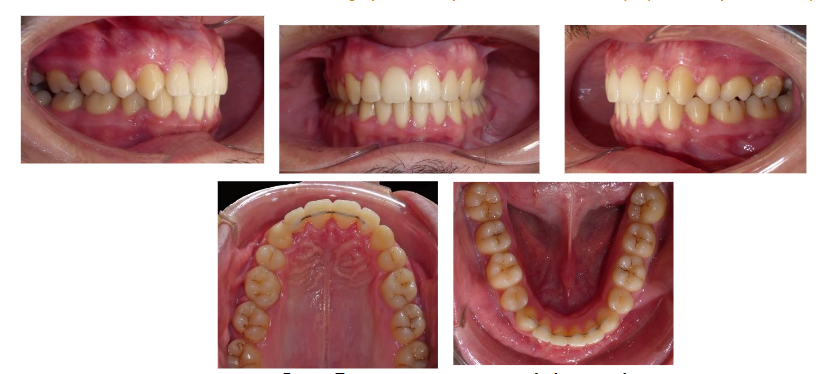

Treatment results:

Our therapeutic objectives were successfully achieved. The patient’s facial profile showed significant improvement, with a harmonious labial ratio and a satisfactory smile line.

From a functional perspective, the patient experienced complete resolution of obstructive sleep apnea, with clinical examination confirming normalization of sleep quality. A Class I canine relationship was established, with midline symmetry of the central incisors, and an ideal overbite and overjet were achieved.

Post-treatment panoramic radiography demonstrated good parallelism of the dental roots, with no signs of root resorption (Fig. 9). Profile cephalometric analysis (Fig. 9), final cephalometric measurements (Tables I and II), and general and regional superimpositions (Fig. 10) all confirmed the restoration of normal dental and skeletal relationships.